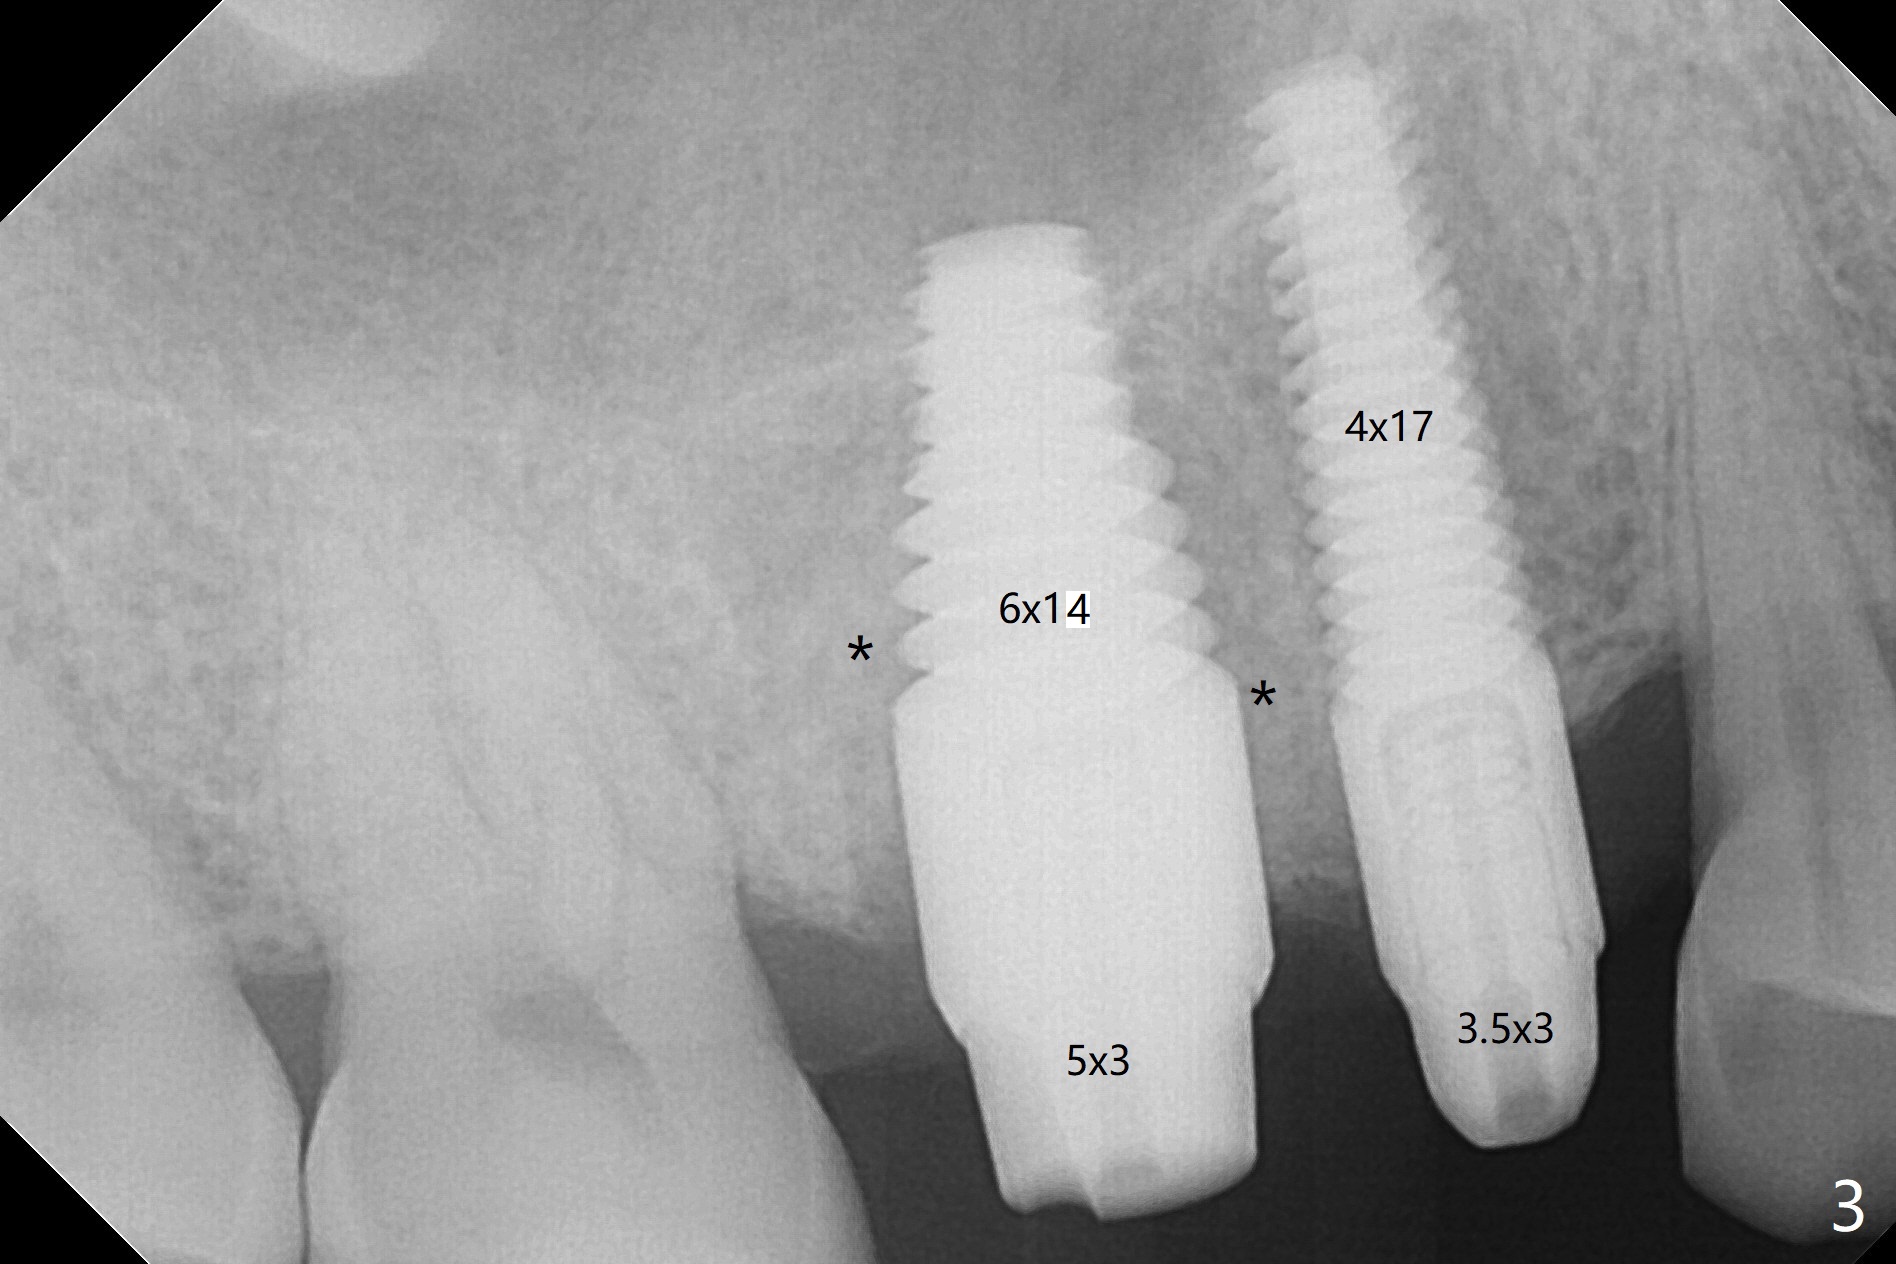

As planned, osteotomy starts at #4 prior to #3 extraction (Fig.1,2). In fact the bone density at the edentulous area is high. Drills are used to finish placing a 4x17 mm tissue-level implant (Fig.3).

A challenge associated with #3 extraction is large amount of granulation tissue apical to the mesiobuccal root (MB, Fig.2 (inset: red dashed line)). To remove the granulation tissue (*) apical to the septum (S), the septum between the buccal roots has to be chiseled. The remaining septum for osteotomy becomes less.

With proper manipulation, a 6x14 mm implant is placed with primary stability (Fig.3). The buccal and palatal socket opening is closed with Vera Graft (allograft, Fig.4 *), which is in turn covered by an immediate splinted provisional. No gap exists 7 months postop (Fig.5,6). Return to Upper Molar Immediate Implant, Prevent Molar Periimplantitis (Protocols, Table), IBS Xin Wei, DDS, PhD, MS 1st edition 09/26/2017, last revision 04/24/2018